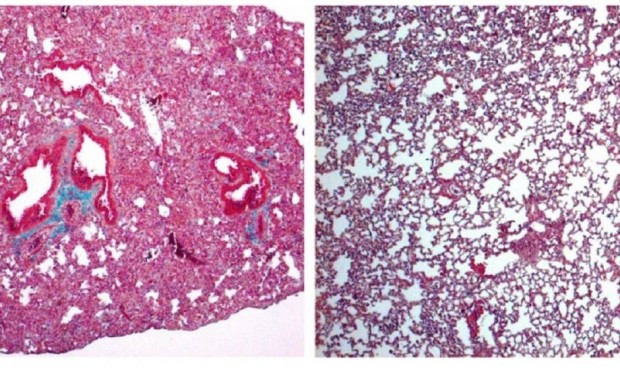

A la izquierda, pulmón de ratón con signos de fibrosis pulmonar grave. A la derecha, pulmón de ratón tratado con cortistatina, en el que el daño es mucho menor./ IPBLN-CSIC

El estudio, publicado en British Journal of Pharmacology, ha demostrado en modelos experimentales preclínicos que la falta de cortistatina provoca una respuesta descontrolada y nociva del sistema inmunitario —la tormenta de citoquinas— y el posterior desarrollo de la reacción fibrótica pulmonar. Por contra, el tratamiento con cortistatina protege frente a las formas graves de daño pulmonar agudo y el síndrome de dificultad respiratoria aguda. Esta característica la convierte en un candidato para tratar la fibrosis más grave causada por Covid-19.